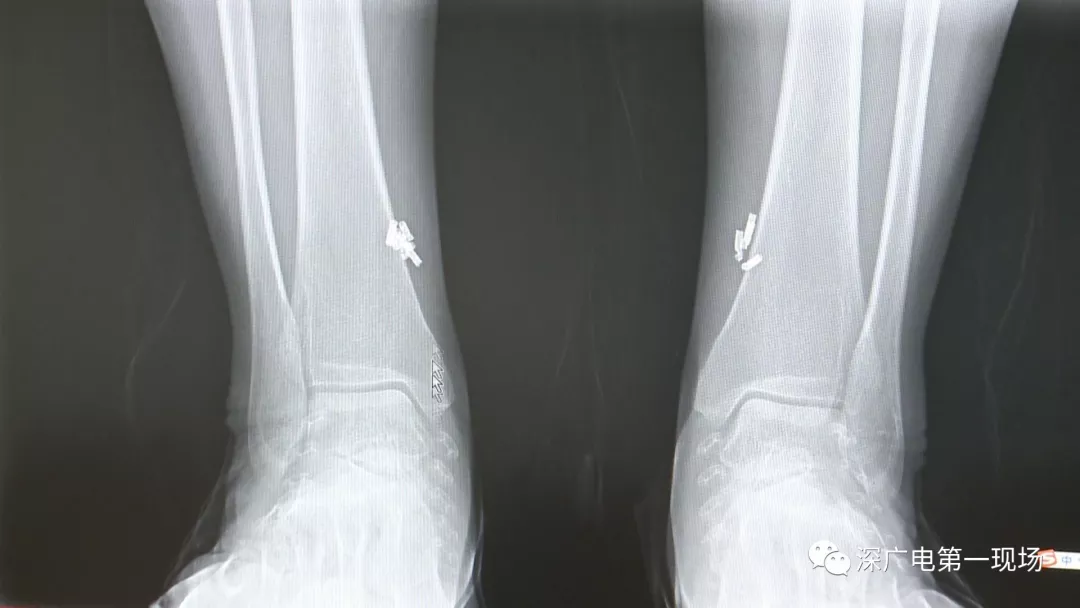

深圳一女子全身被植入彈簧圈,數(shù)量多到驚人!竟是為治這病…

出于保護(hù)患者,我們沒有直接采訪,但是通過醫(yī)生的介紹,記者了解到,病人是個(gè)36歲的女性,2歲開始就有癲癇病史,而且藥物治療也并不見效。

多方打聽之后,在山東某診所用全身埋彈簧圈的方式治療癲癇。陶主任介紹,這樣的方式想要治愈,那幾率也等同于撞大運(yùn)??!

陶醫(yī)生介紹,目前并沒有看到一個(gè)特別正規(guī)的報(bào)道,說這種方法到底治了多少病人,總體的治愈率是多少,有多少病人能夠發(fā)作減輕,這個(gè)是沒有看到。